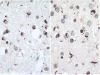

It has been only 5 years since the identification of TDP-43 as the major protein component of the ubiquitinated inclusions in FTLD-U. At that time, there were approximately a dozen papers about TDP-43; today, a "TDP-43" search reveals almost 600 papers. It is now clear that the majority of FTLD cases containing tau- and alpha-synuclein-negative, ubiquitin-positive inclusions (FTLD-U) are FTLD-TDP. The spectrum of TDP-43 proteinopathies includes FTLD-TDP with or without ALS, with or without mutations in GRN, VCP, or TARDBP, with or without chromosome 9p linkage, and sporadic and non-SOD1 familial ALS with or without FTLD-TDP. There are four sub-types of FTLD-TDP, and these correlate with specific clinical and genetic profiles. Sub-types are determined by the presence, predominance, and distribution of the various TDP-43 immunopositive insoluble aggregates-neuronal cytoplasmic inclusions, neuronal intranuclear inclusions, and dystrophic neurites. In this paper, FTLD-TDP pathologic sub-types will be described, and examples of each sub-type will be shown, and implications for future research will be discussed.